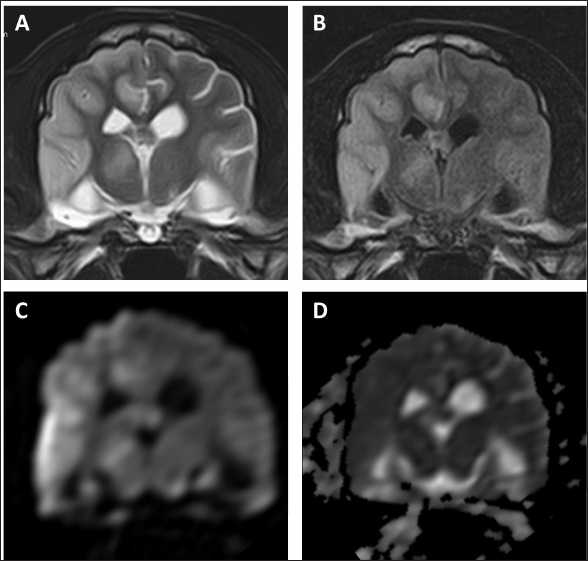

On day 99, the patient presented with acute onset of somnolence and recumbency. Cerebral infarction was suspected because the entire right cerebral hemisphere and part of the thalamus showed high signal intensity on T2WI and FLAIR images, high signal intensity on diffusion weighted Imaging (DWI) images, and equal signal intensity on the ADC map (Fig. 4). MRI at this time demonstrated that the HS lesion in the left frontal lobe was 28.1 × 24.3 × 22.2 cm in size and had clearly regressed (Fig. 1G–I). The patient was also prescribed rivaroxaban (0.25 mg/kg, twice a day; Xarelto tablets 10 mg; Bayer Yakuhin, Osaka, Japan), and the owners were instructed to perform follow-up at home. The patient's neurological symptoms gradually improved, and a third dose of ACNU was administered at 20 mg/m2 on day 110. However, on day 124, an MRI was performed because a neurological examination revealed a decrease or loss of facial sensation, and trigeminal nerve injury was suspected. Although a contrast agent could not be used because the procedure was performed without anesthesia, clear re-enlargement of the HS lesions was observed (Fig. 5). ACNU was therefore changed to temozolomide (Temozolomide Tablets 20 mg “NK,” Nippon Kayaku, Tokyo, Japan), which was administered at an oral dose of 120-140 mg/m2 once daily for 5 days over a 28-day cycle on day 131, 153, and 173. During this time, there were no major changes in the patient's clinical symptoms, and the patient was able to walk with some unsteadiness. However, the patient died suddenly on day 195. A pathological autopsy was not performed at the owner's request.

Fig. 4. MR images of the case at the level of thalamus on day 99. The entire right cerebral hemisphere and part of the thalamus showed a high signal on (A) T2-weighted and (B) FLAIR images, a high signal on (C) DWI images, and an equal signal on (D) ADC-map.